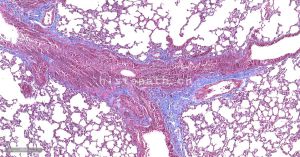

常规病理检测服务